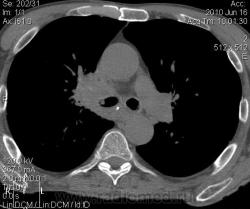

Мужчина 69 лет, с последствием ОНМК находился в доме-интернате для инвалидов. В анамнезе пневмония справа и исходом в пневмосклероз. ФЛГ не проходил 1.5 года. Анализы: СОЭ 20 мм/ч, остальное - без особенностей. Поступил в неврологическое отделение с диагнозом: повторное ОНМК. Невролог заподозрил метастазы головного мозга, направил на рентгенографию легких. После выявленых изменений в правом легком, пациент направлен на КТ головного мозга и грудной полости. От контрастирования и бронхоскопии категорически отказался.

По поводу подозрения на туберкулез пациента в прошлом нодократно проверяли, исключили. ФЛГ архива у меня нет. Все только со слов пациента. Кальцинаты в корне массивные. Трудно сказать, откуда опухоль (если это не конгломерат лимфоузлов!) плотностью 35 ед.Н - то ли из вехнедолевого бронха, который имеет культю 0.4 см и заканчивается выпуклым контуром, но при этом сохраняется воздушность почти всей доли; то ли периферический с центром в прикорневой зоне и вторичным прорастанием ВДБ. К сожалению забыла про снимок легких, на днях выставлю. Я первоначально считала периферический (верхушка, на фоне пневмосклероза) с мтс средостения. По плотности на верхушке узелок 5 ед.Н, только поэтому засомневалась, где же первичный. Лимфоузлы средостения множественные, до 2 см. Кроме того, на верхней стенке правого главного бронха есть мелкое образование такой же 35 е.Н плотности, то ли аденома, то ли прорастает... Без бронхоскопии - только гадать

это периферический рак S2 в/доли правого легкого с мтс во внутригрудные л/узлы.

А тут нечего гадать - данную демонстрацию можно поместить в учебник: узловое образование, с бугристыми, лучистыми контурами, связаное с плеврой, "дорожкой" к корню, перифокальной инфильтрацией. Корень расширен полицикличен за счет конгломерата увеличеных бронхопульмональных, трахеобронхиальных и бифуркационных л/узлов, значительно сдавливающих в/долевой бронх, с нарушением вентиляции в/доли.

Центральный рак ВДБ справа с мтс в л/узлы паратрахеальные нижние, верхние справа, БФ. МТС в головной мозг. А про печень мало сканов

Мне кажется в 6 сегменте печени мтс + еще мтс поражение левого надпочечника вероятнее всего. Мтс в нижние паратрахеальные (с обеих сторон)+бифуркационные л/у. Поражения верхних паратрахеальных не вижу (на коронарах), аксиалы - не показыны сканы выше верхнего края дуги аорты, так что я бы не говорил про поражение верхних медиастинальных лимфоузлов (хотя тут это уже не принципиально) + мтс в головной мозг. А так - центральный рак правого легкого.